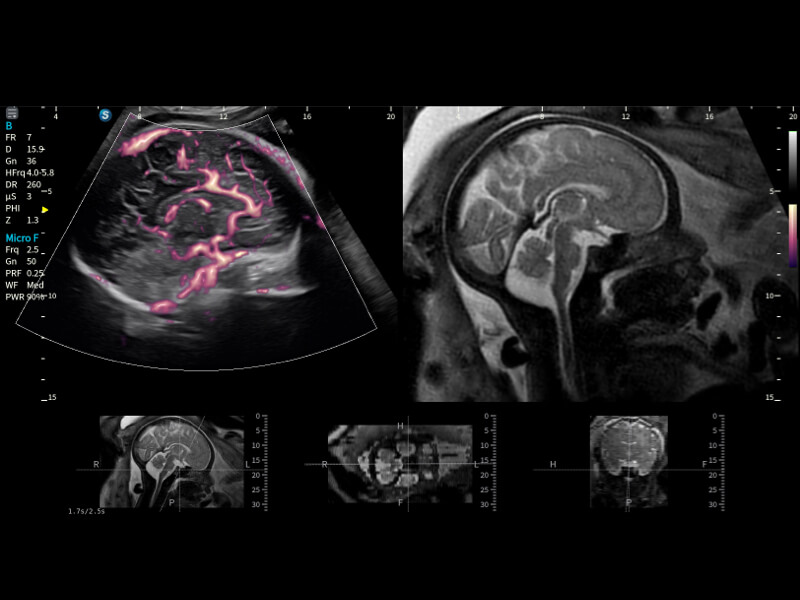

作为开立医疗全新打造的超高端旗舰超声产品,从探头抬起唤醒开启扫查到多维探头发射接收,通过先进的场成像发射、自适应聚合重建等技术,基于RF Data原始射频数据在图像生成、高端功能等方面实现突破,为妇产科、儿科提供全方位临床解决方案。

丰富的血流动力学检测技术,可在不同医疗场景中高效捕捉血流信号,助力临床诊疗。

在传统血流的基础上优化扫查和算法策略,能够更好的抑制组织信息,提炼红细胞运动信息,得到更高帧频,高灵敏度和分辨率的血流信号,还原更真实的血流动力学。

通过光照模型,使二维血流显示出立体的效果,增加血流的敏感性、成束性,减少外溢。可以和其他不同的血流技术联合使用,融合不同技术的优势。轻松应对微小血管,增强血流的立体效果,提升视觉敏感性。

通过创新的Matrix E自适应滤波算法,能有效滤除软组织和噪声信号,最大限度保留超低速微细血流的信号;结合超长时间域算法,极大提升细微血流的敏感性和空间分辨率,更真实的反应组织、包块的血流灌注情况。